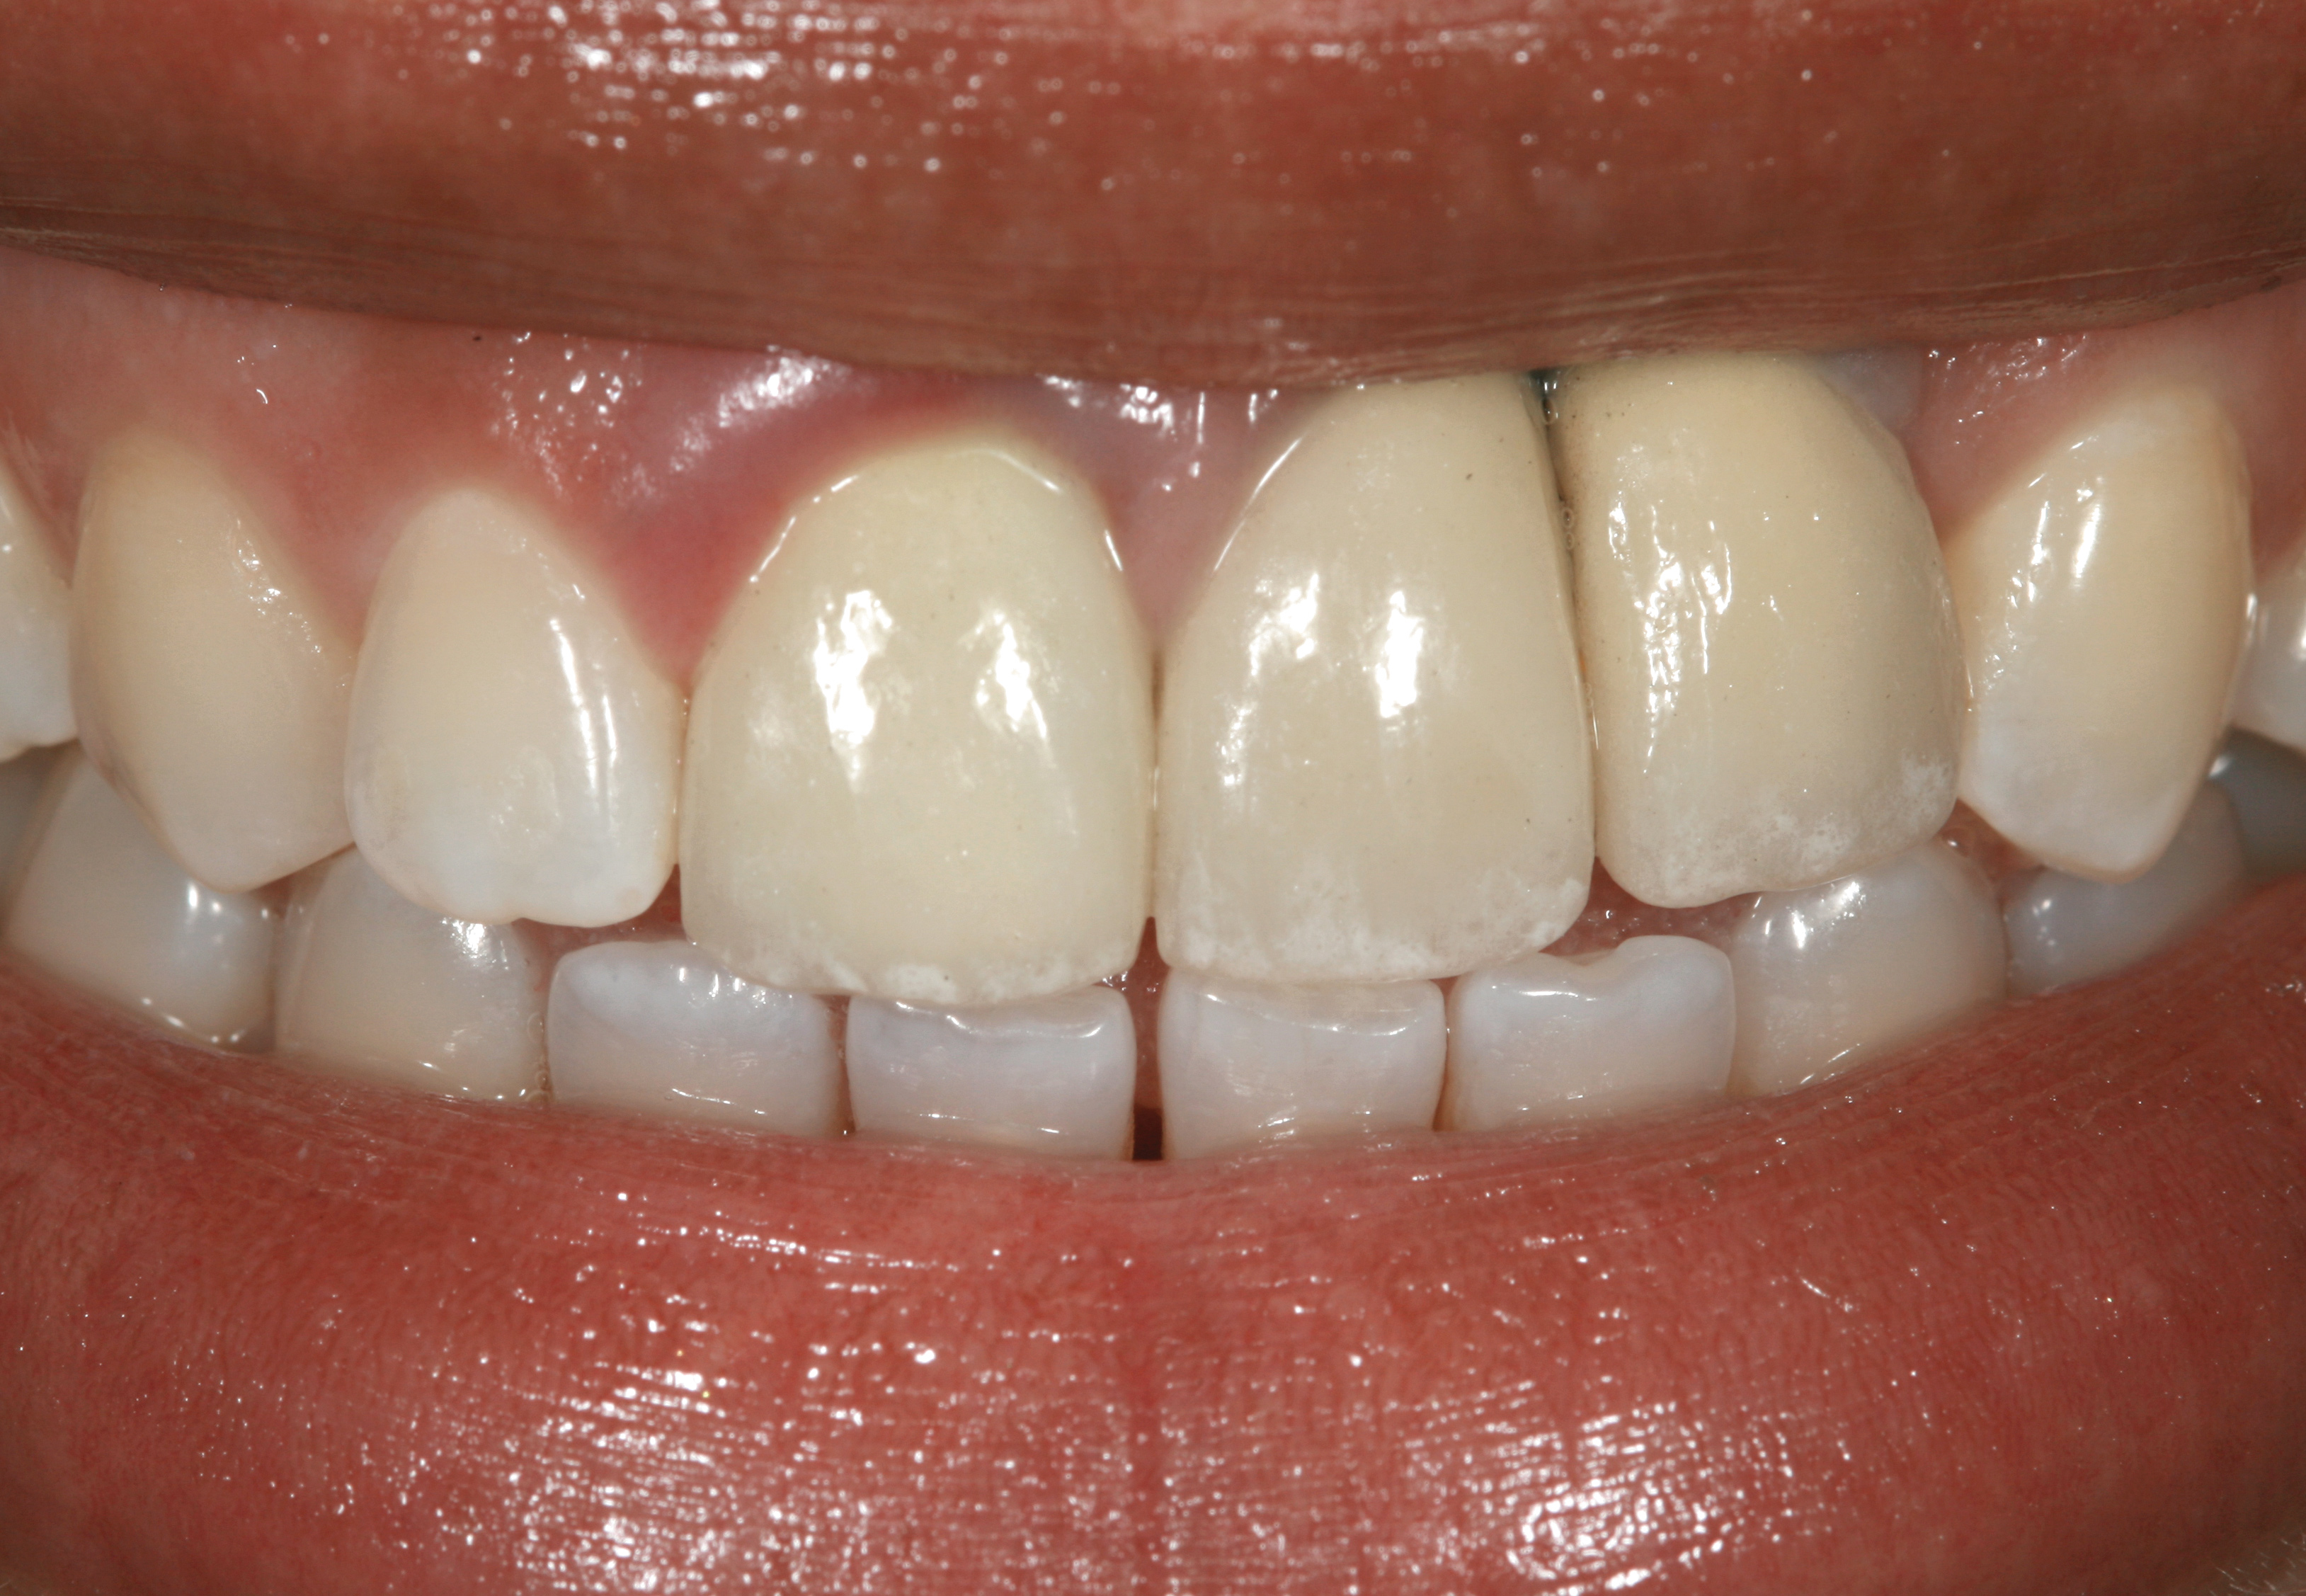

Fig 3. A patient presented with a high smile line and midfacial recession of the maxillary right lateral incisor as evidenced by the increased tooth length compared with the contralateral lateral incisor.

Figure 3

Fig 4. Intraoral view of tooth No. 7 with the gingival zenith more apical than the adjacent central incisor and canine tooth.

Figure 4

The following case report provides an example of this case scenario: A 28-year-old white female patient presented with her maxillary right lateral incisor significantly longer than the contralateral tooth following restoration of an existing crown that was 10 years old (Figure 3). The patient was dissatisfied with the esthetic appearance of the restoration due to the increased length, recession of the gingival tissues, and discoloration of the surrounding mucosa (Figure 4). Similar to case scenario No. 1, the first step in treatment was to decoronate the healthy implant by placing a flat surgical cover screw and employing a provisional resin-bonded-retained (RBR) prosthesis as a transitional fixed restoration (Figure 5 and Figure 6). The gingival augmentation in situ was allowed to take place for 2 to 3 weeks and was evaluated after that time (Figure 7).